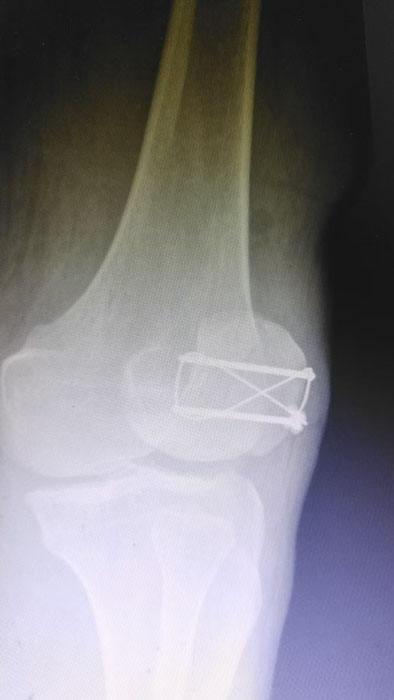

何店鎮(zhèn)中心衛(wèi)生院成功開展髕骨鋼板內(nèi)固定手術(shù)

——何店鎮(zhèn)中心衛(wèi)生院成功開展髕骨鋼板內(nèi)固定手術(shù)

隨州新聞網(wǎng)訊 (通訊員王靜、陳勇)為深入推進(jìn)緊密型醫(yī)共體建設(shè),切實(shí)讓轄區(qū)群眾在家門口就能享受到優(yōu)質(zhì)、便捷的醫(yī)療服務(wù),以醫(yī)療便民舉措為優(yōu)化營商環(huán)境注入健康活力,3月31日中午,何店鎮(zhèn)中心衛(wèi)生院(隨州市曾都區(qū)人民醫(yī)院何店分院)依托醫(yī)共體資源優(yōu)勢,特邀曾都區(qū)人民醫(yī)院脊柱創(chuàng)傷外科主任徐三軍到該院,成功為一名47歲髕骨骨折患者實(shí)施髕骨骨折切開復(fù)位內(nèi)固定手術(shù),用專業(yè)診療守護(hù)群眾健康,用務(wù)實(shí)行動踐行便民宗旨。

精湛施術(shù) 安全有序,守護(hù)患者健康

手術(shù)現(xiàn)場,徐三軍主任憑借多年積累的臨床經(jīng)驗(yàn)和嫻熟的手術(shù)技巧,精準(zhǔn)完成骨折復(fù)位、鋼板內(nèi)固定、傷口縫合等一系列關(guān)鍵操作,動作規(guī)范流暢、精準(zhǔn)高效,最大限度減少手術(shù)創(chuàng)傷。該院外科醫(yī)護(hù)團(tuán)隊(duì)全程密切配合、協(xié)同發(fā)力,嚴(yán)格按照手術(shù)規(guī)范操作,全程嚴(yán)密監(jiān)測患者心率、血壓等生命體征,及時應(yīng)對術(shù)中各類突發(fā)情況,全力保障手術(shù)安全。此次手術(shù)全程順利,術(shù)中出血量少,患者生命體征始終平穩(wěn),術(shù)后患者順利安返病房,為后續(xù)康復(fù)治療奠定了堅(jiān)實(shí)基礎(chǔ)。